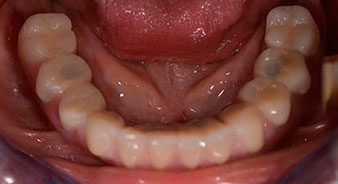

The 64-year-old patient presented with residual dentition of teeth 38, 33 and 43 and a clasp denture in the mandible (Fig. 1 and 2).

Following an explanation of the various treatment options open to her, the patient decided on extraction of the residual dentition in the mandible, an immediate implantation and treatment with the Fast & Fixed method (bredent medical), whereby the provisional fixed denture is screwed onto four implants on the same day as the surgery. The goal was to operate on the patient on the Friday so that she could assist in the oral examinations on the following Monday.

A three-dimensional cone beam computed tomography scan (CBCT, Planmeca) was performed to aid planning and minimize risks. This revealed that the quality and quantity of the available bone were sufficient for the surgery and immediate restoration using the Fast & Fixed method. Following the protocol for this concept, the implants are inserted at 35, 32, 42 and 45. Angling the distal implants by up to 45° shifts the emergence profile to posterior and generates a larger support polygon (Fig. 3).